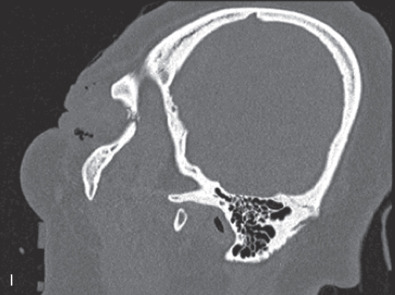

The gold standard for radiographic evaluation is thin-slice helical computed tomography (CT). Midface fractures are confirmed by axial, coronal, and sagittal views. The degree of comminution, bone loss, and detailed images of the fracture patterns can be assessed and juxtaposed to surrounding soft tissue structures. 3D reconstruction, when utilized, can aid in visualizing the complex 3D anatomical orientation of fracture fragments that occur in Le Fort injuries and facilitate reconstructive planning.

Le Fort III fractures generally consist of a combination of fractures that involve the palatine bones, the maxilla, the pterygoid plates, the nasal bones, lacrimal bone, and zygomas; they essentially separate the face along the base of the skull. The fracture pattern extends through the nasofrontal suture along the medial wall of the orbit, through the inferior orbital fissure and the lateral orbital wall to the zygomaticofrontal suture. In addition, the zygomaticotemporal suture is separated. The fracture extends across the sphenoid bone resulting in dysjunction at the pterygoid plates ( Figs. 1.13.16 and 1.13.17 ). The septum is separated from the cribriform plate of the ethmoid. Pure Le Fort III fractures are rare, and in actuality, most are ZMC fractures in conjunction with Le Fort I and II fractures lending the appearance of a comminuted “Le Fort III.” The force is delivered from the orbital level, resulting in craniofacial dysjunction. The fracture is generally more comminuted and more extensive on the side of force application.